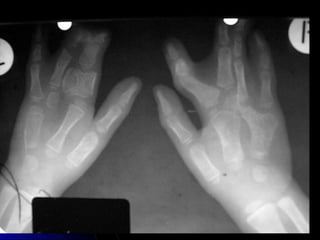

MANO PA

Estructuras Visualizadas

•Metacarpianos 1-5

•Carpianos - Escafoides,

Semilunar, Piramidal, Pisiformes,

Trapezio, Trapezoides, Hueso

Grande, Ganchoso

•Falanges Proximales y Distales 1-

5

•Falanges Medias 2-5

•Falanges Distales 1-5

•Cubito & Estiloides Cubital

MANO PA - MARCADO